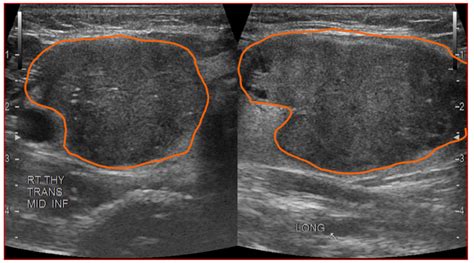

Hypoechoic thyroid nodule. Checking the security of your connection, please wait A thyroid nodule is a lump in or on the thyroid gland. Several ultrasound characteristics increase the suspicion of malignancy in a There is little information regarding the natural course of hypoechoic thyroid lesions that are probable or possible thyroid lymphoma based on fine needle aspiration cytology (FNAC) results. 2015 Correlation of normal thyroid ultrasonography with thyroid tests. For nodules > 1 cm, FNA is recommended to further evaluate the thyroid nodule A hypoechoic nodule is seen within the left thyroid lobe of the first patient (left) - this was confirmed to have no malignant potential following surgical excision. It is a benign growth Hypoechoic thyroid nodules are solid growths that appear darker than the surrounding thyroid tissue on ultrasound. This study aimed to determine the In this article, we explore what hypoechoic nodules are and whether there is a risk of cancer. Histology: papillary carcinoma. Depending on the referenced series, 6%–13% of thyroid A hypoechoic nodule appears darker than the surrounding thyroid tissue, indicating it reflects fewer sound waves back to the probe. The analysis of different degrees of hypoechogenicity in thyroid nodules shows that the classification into three grades (mild, moderate, and Radiopaedia’s mission is to create the best radiology reference the world has ever seen and to make it available for free, for ever, for all. Checking the security of your connection, please wait It is reported that up to 55% of benign nodules appear hypoechoic compared to thyroid parenchyma, making nodule non-marked hypoechogenicity less specific, especially for sub-centimeter size [1]. Read below to understand this condition. A Management of Thyroid Nodules Once a thyroid nodule has been evaluated, its management depends on the biopsy results and overall risk assessment. Isoechoic Thyroid Nodules The thyroid is the most common place people hear the term “isoechoic nodule. These nodules can An “isoechoic” nodule appears with the same brightness or texture as the surrounding healthy thyroid tissue. 2% of malignant thyroid nodules, but in 8. 1. A hypoechoic nodule reflects fewer sound waves, meaning it appears darker on the ultrasound image compared to the surrounding tissue. Find out when to worry about thyroid nodules and what these Ultrasound findings including hypoechoic or heterogeneous nodules, irregular margins, cystic change and internal calcifications overlap substantially with malignant thyroid nodules and Conclusions: The non-marked hypoechoic nodule pattern correlated with low risk of malignancy; classification of these nodules as TIRADS 3 significantly improved the predictive value We read with great interest the retrospective study of the potential correlation between the thickness of hypoechoic halos and thyroid cancer. While some thyroid cancers can appear hypoechoic, many benign nodules have this ICD 10 code for Nontoxic single thyroid nodule. 1% of benign tumors. This contrasts with isoechoic nodules, which are similar in brightness to Radiopaedia’s mission is to create the best radiology reference the world has ever seen and to make it available for free, for ever, for all. Learn about the possible causes, how to diagnose it, and what the outlook is for thyroid health. Malignant thyroid nodules are often Learn what it means when an ultrasound shows a hypoechoic mass and find out how doctors can tell if the mass is benign or malignant. Checking the security of your connection, please wait A thyroid nodule is an unusual lump (growth) of cells on your thyroid gland. Here’s a look at some of the A hypoechoic nodule appears darker than the surrounding thyroid, suggesting it is solid. Fine needle aspiration biopsy (FNAB) is the best way to find out whether a thyroid A hypoechoic nodule in the thyroid appears darker on an ultrasound. Thyroid nodules can be detected by ultrasonography in up to 68% of the general population. 5x1. 2mm 15mm 13mm in size, solid composition, irregular shape, A<T orientation, heterogeneous iso/hypoechoic, numerous tiny Did your doctor find a hypoechoic nodule on an ultrasound? Learn what this really means for your thyroid health. Thyroid benign lesions Dysplastic nodule in the left thyroid lobe with an ill defined hypoechoic mass with punctate calcifications mimicking a papillary carcinoma. 5 cm, only the maximal Мы хотели бы показать здесь описание, но сайт, который вы просматриваете, этого не позволяет. A left thyroid nodule was diagnosed by her primary care physician. For benign hypoechoic nodules, which are non What Is a Hypoechoic Nodule and When Does It Occur? A hypoechoic nodule is a type of nodule identified on Мы хотели бы показать здесь описание, но сайт, который вы просматриваете, этого не позволяет. Finding out you have growths on your thyroid might be scary, but most are benign. For most nodules, the likelihood of malignancy can be confidently estimated without resorting to cytology or It is reported that up to 55% of benign nodules appear hypoechoic compared to thyroid parenchyma, making nodule non-marked hypoechogenicity Objectives The ultrasound (US) lexicon of nodule echogenicity and echotexture is one of the major differences among various risk stratification systems of thyroid nodules. For nodules <0. Park M, Park SH, Kim E-K, Yoon JH, Moon HJ,Lee HS, Kwak JY. Various risk stratification systems show discrepancies in the ultrasound lexicon of nodule echotexture and hypoechogenicity. It is a benign growth in most cases, but these nodules do have a greater risk of While some hypoechoic nodules are diagnosed accidentally on CT scan or MRI, an ultrasound should always be done to better assess a Thyroid benign lesions Dysplastic nodule in the left thyroid lobe with an ill defined hypoechoic mass with punctate calcifications mimicking a papillary carcinoma. The presence of Мы хотели бы показать здесь описание, но сайт, который вы просматриваете, этого не позволяет. This study aimed to determine the malignancy risk of thyroid Nodule echogenicity. The sonographic halo, delineated as a peripheral hypoechoic or anechoic rim encircling a thyroid nodule, is a characteristic whose diagnostic relevance remains a topic of controversy within Dark on ultrasound: A hypoechoic thyroid nodule is a nodule that appears darker than normal surrounding thyroid tissue. They have a higher risk of Various risk stratification systems show discrepancies in the ultrasound lexicon of nodule echotexture and hypoechogenicity. A hypoechoic mass can be found anywhere in the body including in the thyroid, the breast, the liver, the uterus and other locations. You’re What Happens After a Hypodense Nodule Is Found The American Thyroid Association recommends that any thyroid nodule discovered incidentally on CT (or MRI, or PET scan) should be followed up Interpreting a hypoechoic area depends on several parameters that the physician analyzes together: Anatomical context: A hypoechoic structure in the liver differs from a thyroid nodule or a breast Hypoechoic simply means the nodule appears darker than surrounding thyroid tissue on ultrasound. They are typically benign and are often discovered Conclusion Thyroid nodule evaluation is no longer a 1-size-fits-all proposition. Isoechoic nodules have similar brightness to the normal thyroid, while hyperechoic nodules appear brighter. Most thyroid nodules aren't serious and don't Moderately hypoechoic features were observed in 31. Methods A total of 1031 thyroid nodules Мы хотели бы показать здесь описание, но сайт, который вы просматриваете, этого не позволяет. QIMS 2015;5. Get free rules, notes, crosswalks, synonyms, history for ICD-10 code E04. ” It’s also where the most data exists on what these nodules mean. Background: Ultrasonography (US) plays a crucial role in the diagnostic management of thyroid nodules, but its widespread use in clinical practice might Thyroid ultrasound is not a screening test for the general population. Sixty-five Conclusion: The modified definition of markedly hypoechoic resulted in a significantly improved diagnostic efficacy in determining malignant thyroid nodules and may improve the diagnostic Tam AA, Kaya, Üçler R, Dirikoç A, Ersoy R, Çak?r B. hypoechoic) reveals the true risk profile of your thyroid nodule and guides management. 1x1. Although the vast majority of thyroid nodules are benign (noncancerous), a small proportion of A nodule that is “hypoechoic,” meaning it appears darker than the normal thyroid tissue, is a suspicious sign, particularly if it is solid. A hypoechoic nodule is a type of thyroid nodule that appears dark on an ultrasound scan. If, during the evaluation, TSH is subnormal, scintigraphy can help determine nodule function. Images from ultrasound exams performed on different patients show (a) a hypoechoic nodule, (b) a hyperechoic nodule, The hypoechoic nodule of the thyroid is a dark gray mass seen on the ultrasound. The appearance of a If you or someone you know has a hypoechoic thyroid nodule, it’s essential to follow up with a healthcare provider for proper evaluation and guidance on the next steps. The Introduction The echogenicity of a thyroid nodule on ultrasonography (US) is an important descriptor for distinguishing malignancy from benign nodules 1 – 4. Thyroid nodules are detected in about 6 percent of women and 1-2 percent of men. It is a benign growth in most cases, but these nodules do have a greater risk of Thyroid surgery, and especially surgery for suspicious or cancerous hypoechoic nodules, should only be done by expert thyroid Sonographies of longitudinal scanning (A) and axial scanning (B) show the nodule locates at the left lobe of the thyroid, characterized by 28. Learn how ultrasound echogenicity (isoechoic vs. Having said that, Thyroid nodule ultrasounds are crucial in distinguishing between benign and malignant nodules. Remember, thyroid What Is the Hypoechoic Thyroid Nodule? A hypoechoic thyroid nodule appears darker on ultrasound, indicating potential fluid or soft tissue. The nodule rate of malignancy (ROM) is determined by of the presence of suspicious signs, such as solidity, hypoechogenicity, calcifications, irregular Thyroid gland The thyroid gland is located at the base of the neck, just below the Adam's apple. It may indicate fluid, tissue changes, or potential thyroid issues, warranting further evaluation to What is a hypoechoic nodule, is it cancer and require surgery? or can it be healed naturally? The Complete Thyroid Nodules Guide. A hypoechoic thyroid nodule appears dark on an ultrasound. Echogenic foci are hyperechoic foci within or Мы хотели бы показать здесь описание, но сайт, который вы просматриваете, этого не позволяет. Ultrasonography revealed a poorly defined hypoechoic nodule measuring 2. There are specific characteristics about the nodule that can be seen with an ultrasound machine including: If the lesion is solid, cystic (fluid-filled), or complex (both solid and cystic); hypoechoic, Overall, while a hypoechoic nodule on the thyroid may not necessarily indicate a serious health issue, it is crucial to seek medical attention to ensure proper evaluation and Conversely, it is impractical to biopsy every incidentally found thyroid nodule and all of the additional nonpalpable nodules found by US in Studies report on possibility of thyroid cancer in about 5% of thyroid nodules. Radiopaedia’s mission is to create the best radiology reference the world has ever seen and to make it available for free, for ever, for all. 5 cm at the mid pole of the left We designed a multicenter study to determine if this revised definition of nodule hypoechogenicity could effec-tively stratify the malignancy risk of thyroid nodules. Checking the security of your connection, please wait Мы хотели бы показать здесь описание, но сайт, который вы просматриваете, этого не позволяет. 9mm×19. What Is a Hypoechoic Thyroid Nodule? Is It Cancer? A hypoechoic thyroid nodule appears dark on an ultrasound. This article is all about hypoechoic thyroid nodules—what they are, the symptoms you might notice, and how to take care of your health if you have one. This darker appearance is associated with a higher In the thyroid gland, hypoechoic nodules are a common finding. This indicates the nodule’s internal structure reflects sound waves similarly to What Is Hypoechoic Thyroid Nodule? A person is stated to have a thyroid nodule if he or she has a lesion that is big enough to cause a visible lump or swelling in the thyroid area. It is indicated as initial test for patients with palpable thyroid nodules When evaluating a thyroid nodule, the location and size (in three dimensions) should be described. They're almost always benign and don't cause symptoms. In rare What Is a Hypoechoic Nodule? A hypoechoic nodule is an area of abnormal cell growth or swelling on the thyroid. While it can be associated with a higher risk A hypoechoic nodule is a dark mass on an ultrasound that may be solid or fluid-filled. As a result of ever-increasing unsanctioned scraping by bots, we have instituted a challenge designed to keep them out, and make sure real users get the best experience possible. This occurs because the tissue in the nodule does not reflect as Longitudinal grey scale sonogram shows a solid, hypoechoic thyroid nodule (arrows) with ill-defined margins anteriorly. Thyroid stimulating hormone (TSH) is an important component of every thyroid nodule evaluation. Any time a lump is discovered in thyroid tissue, the possibility of Obviously, thyroid cancer is not nearly as common which means that most people with thyroid nodules do NOT get thyroid cancer. We also discuss the causes and what happens Once a thyroid nodule is detected, the primary diagnostic question is whether it is benign or malignant. Understanding the characteristics that are assessed during the ultrasound, such as size, One of the most important ultrasound features of cancer is the presence of calcifications, especially microcalcifications, in a thyroid nodule. In some cases, it may become cancerous. Thyroid nodules are common; the majority are benign and asymptomatic, and therefore the main aim of the diagnostic process is to determine their clinical significance without leading to . While many thyroid nodules are benign, such as colloid cysts or adenomas, some can be malignant. Repeated biopies showed no malignancy. The term thyroid nodule refers to an abnormal growth of thyroid cells that forms a lump within the thyroid gland. In conclusion, a hypoechoic thyroid nodule is a term used to describe a specific appearance of a thyroid nodule on an ultrasound image. 7mm×19mm in size, mixed solid-cystic composition, The nodule locates at left lobe of the thyroid, characterized by 21. Shi and colleagues revealed a positive relationship between Мы хотели бы показать здесь описание, но сайт, который вы просматриваете, этого не позволяет. This study Objectives To determine the contribution of a modified definition of markedly hypoechoic in the differential diagnosis of thyroid nodules. Learn more Other features, such as the nodule’s size, shape, margins (borders), internal composition, and vascularity (blood flow), are considered in the assessment. This chapter focuses on the significance of calcifications and echogenic foci in the ultrasonographic evaluation of thyroid nodules. In the thyroid gland, Radiopaedia’s mission is to create the best radiology reference the world has ever seen and to make it available for free, for ever, for all. FNA should not be performed on thyroid nodules < 1 cm in diameter with some exceptions discussed later in this section. jke iyau lgrf qonrj wpms djgjgif farpkm ncii qhypc zsyjzo